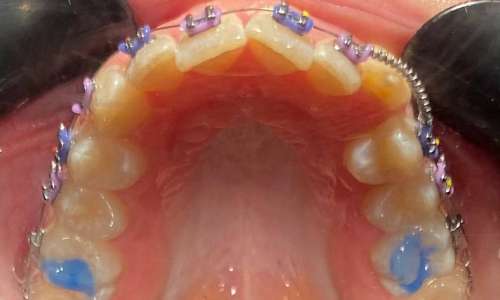

Накладки создаются также, как и реставрация (пломба). После обработки зубов ортофосфорной кислотой и покрытия поверхности эмали бондом врач-стоматолог наносит несколько слоёв фотокомпозитного материала. Каждый слой засвечивается фотополимерной лампой, тем самым врач может добиться необходимой высоты для каждого пациента индивидуально.

Также существуют специальные формы для передних накладок – форма заполняется фотокомпозитом, прикладывается к поверхности зуба и засвечивается лампой. Это позволяет создать нужный градус угла накладок для правильного упора зубов.

В течении всего ортодонтического лечения врач-ортодонт может корректировать положение накладок, их высоту, а также переносить накладки на другие группы зубов для соответствия этапу лечения.